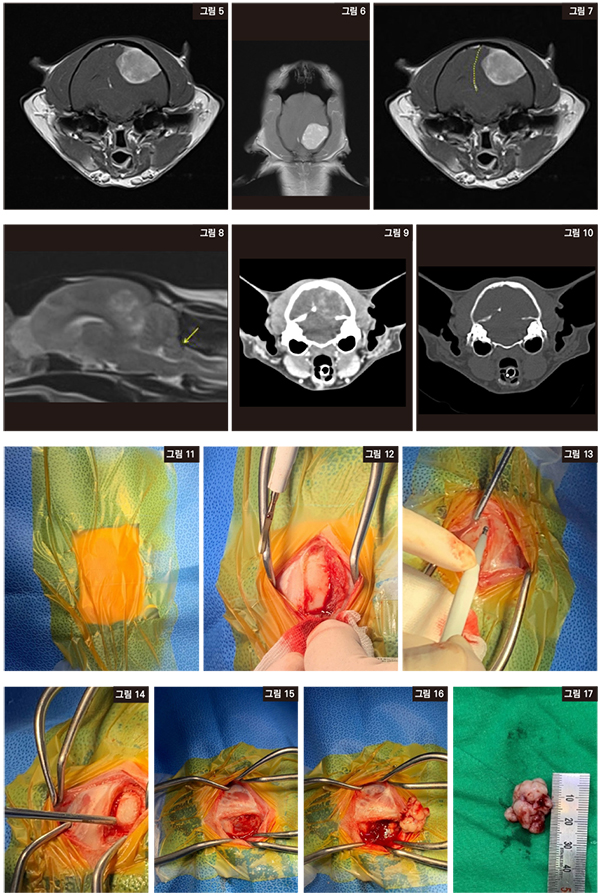

내원 당일 MRI를 촬영했다. [그림 5, 6]의 T1 조영상에서 좌측 occipital lobe과 parietal lobe수준에서 뚜렷한 조영증강을 보이고, dural tail sign을 동반한 종괴가 관찰되었다. Meningioma가 의심되었다.

[그림 7, 8]에서 종괴로 뇌축이 우측으로 변위되었고, 소뇌가 압박되어 foramen magna로의 소뇌 herniation이 관찰되어 뇌척수액 채취는 진행하지 않았다.

다음날 CT촬영을 진행 후 수술을 진행하였다. [그림 9, 10]에서 CT 판독 결과 meningioma는 blood brain barrier(BBB)의 영향을 받지 않는 extra-axial tumor로 뚜렷한 조영증강이 관찰되었고, 종괴와 인접한 소뇌천막(tentorium)의 lysis 소견이 관찰되었다.

수술을 진행했다. Position은 sternal recumbency로 머리를 60도로 구부렸고, 기도유지에 주의했다. 앞에서 기술한 lateral craniectomy를 실시했다[그림 11, 12, 13, 14]. 두개골을 제거한 사진이다[그림 15]. 종양을 제거한 사진이다[그림 16, 17].